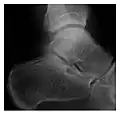

Figure 3: A 26-year-old man presenting with wrist pain after being assaulted. (a) Initial anteroposterior radiograph shows a subtle linear lucency within the scaphoid extending to the scaphocapitate articular surface that was overlooked (arrow). (b) Initial "scaphoid" view was negative. (c) Followup anteroposterior radiographs, 12 days later, shows obvious scaphoid fracture (arrows).[1]

Triquetral fracture usually occurs on the dorsal aspect by impingement from the ulnar styloid or avulsion of strong ligamentous attachment. The dorsal avulsion fracture or "chip fracture" appears as a small bony fragment on the dorsal aspect of the triquetrum and is best detected on the lateral view(Figure 4). When radiography is negative in patients with high suspicion of a fracture, both MRI and MDCT will be of value. However, it has been shown that MRI is superior for detecting trabecular fractures in carpal bones.